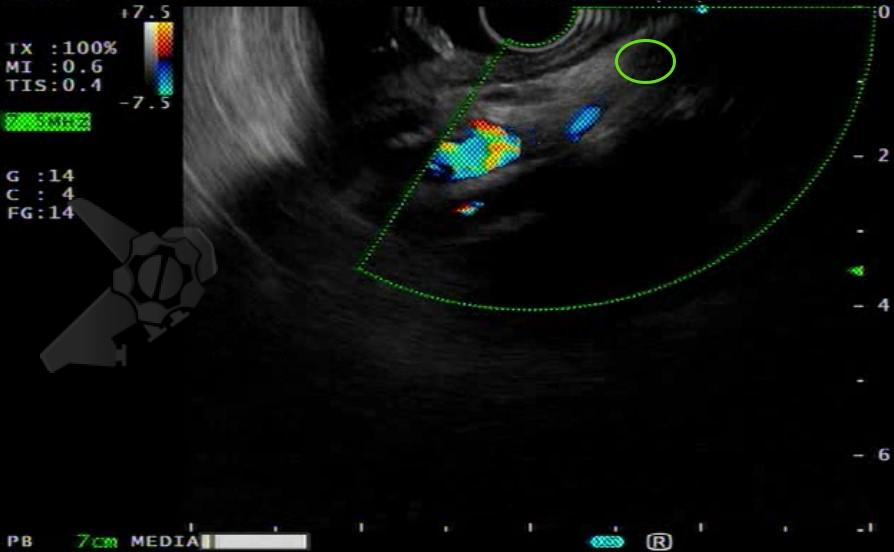

Após preparo colônico com manitol e a realização de uma nova radiografia, que não apontou qualquer mudança na posição inicial da prótese dentária desde a admissão, o paciente foi submetido a colonoscopia. Até a intubação cecal o corpo estranho não foi encontrado, com presença de doença diverticular no hemicólon esquerdo (foto 2 e 3).